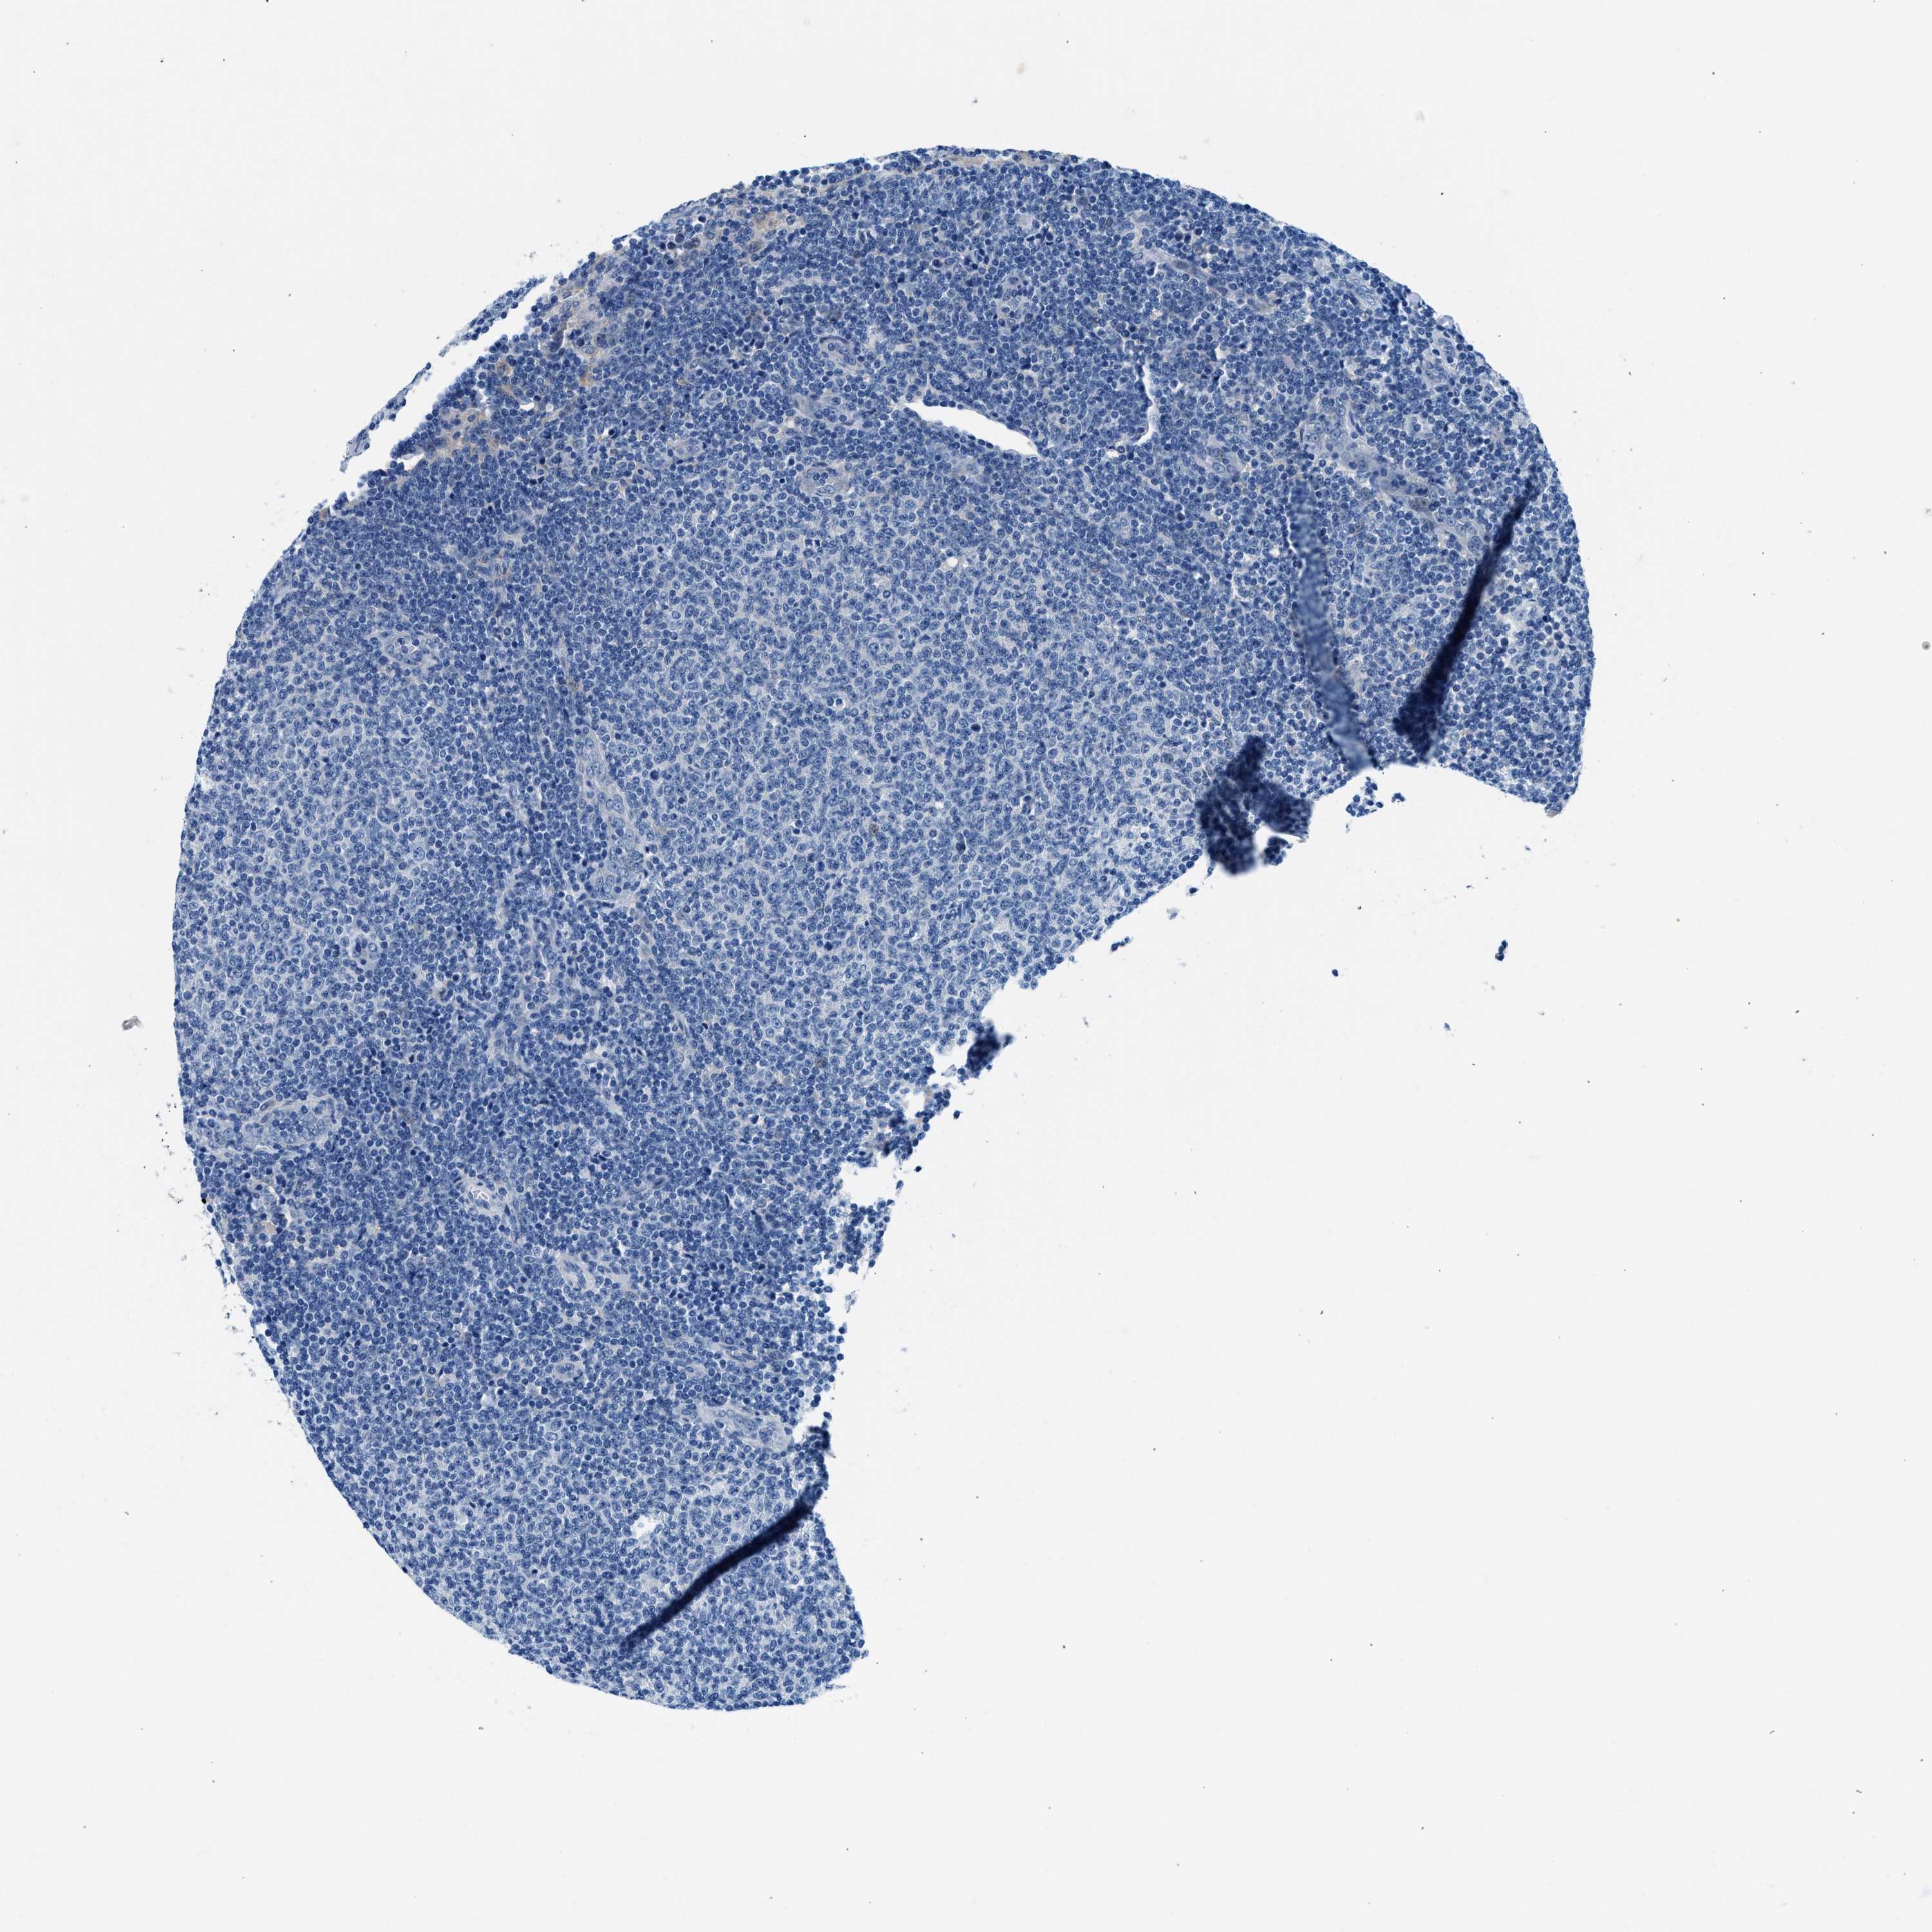

CANCER LYMPHOMA Show tissue menu

LYMPHOMA - Protein expressioni

A mouse-over function shows sample information and annotation data. Click on an image to view it in a full screen mode. Samples can be filtered based on level of antibody staining by selecting one or several of the following categories: high, medium, low and not detected. The assay and annotation is described here.

Antibody stainingi

Antibody staining in the annotated cell types in the current human tissue is reported as not detected, low, medium, or high, based on conventional immunohistochemistry profiling in selected tissues. This score is based on the combination of the staining intensity and fraction of stained cells.

Each image is clickable and will lead to virtual microscopy that enables deeper exploration of all samples and also displays staining intensity scores, fraction scores and subcellular localization as well as patient and tissue information for each sample.

Antibody HPA016867

Antibody HPA018271

Hodgkin's disease, NOS

Malignant lymphoma, non-Hodgkin's type, High grade

Malignant lymphoma, non-Hodgkin's type, Low grade